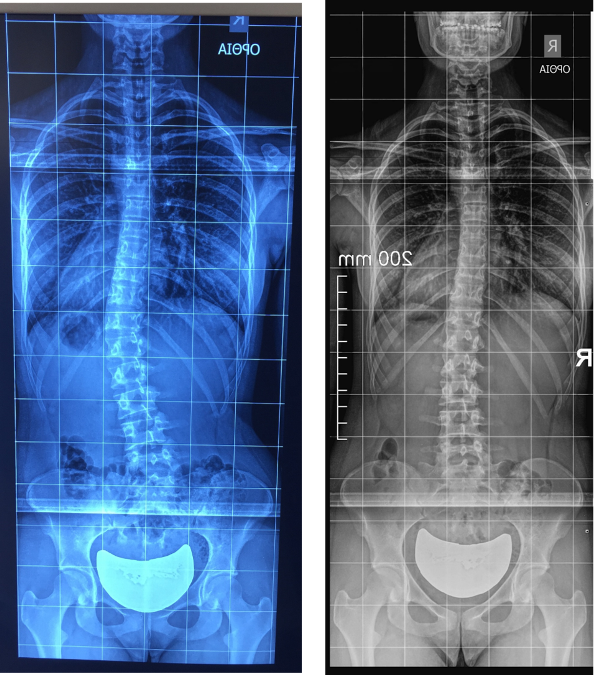

- Physiotherapeutic Scoliosis Specific Exercises (PSSE): Recent evidence for their effectiveness in scoliosis treatment and the position of the International Scientific Societies, an updated review

- ApiFix treatment for Adolescent Idiopathic Scoliosis (AIS): The importance of Schroth method exercises after the minimal invasive operation

Σκοπός της πρώτης έρευνας είναι να παρουσιάσει τις πρόσφατες επιστημονικές αποδείξεις για την αποτελεσματικότητα των Ειδικών Φυσικοθεραπευτικών Ασκήσεων για την Σκολίωση (PSSE) και να αναλύσει την επίσημη θέση των διεθνών επιστημονικών κοινοτήτων που ασχολούνται με την αντιμετώπιση της σκολίωσης. Πλέον, μετά την δημοσίευση υψηλής μεθοδολογικής ποιότητας ερευνών τα τελευταία χρόνια (Randomised Control Trials -RCT), δεν υπάρχει αμφιβολία για την αποτελεσματικότητα των PSSE και το επίπεδο επιστημονικών αποδείξεων θεωρείται Level of Evidence I. Επίσης, όλες οι διεθνείς επιστημονικές κοινότητες που ασχολούνται με την θεραπεία της σκολίωσης, με κοινή τους δημοσίευση, αποδέχονται τον σημαντικό ρόλο των PSSE στον περιορισμό της επιδείνωσης της σκολίωσης και τις αναγνωρίζουν σαν το πρώτο βήμα αντιμετώπισης σε μικρές σκολιώσεις κάτω από 25 μοίρες. Σε μεγαλύτερες σκολιώσεις, όταν υπάρχει ένδειξη για εφαρμογή κηδεμόνα, αυτός πάντα θα πρέπει πάλι να συνοδεύεται από τις PSSE, οι οποίες φαίνεται να βελτιώνουν σε σημαντικό βαθμό το τελικό θεραπευτικό αποτέλεσμα.

Σκοπός της δεύτερης έρευνας είναι η παρουσίαση των αποτελεσμάτων από την εφαρμογή του συστήματος ApiFix στην Ελλάδα, καθώς και η σημαντικότητα των ασκήσεων της μεθόδου Schroth, οι οποίες εφαρμόζονται πριν και μετά από την μικροεπεμβατική τεχνική για την χειρουργική διόρθωση της σκολίωσης. Η έρευνα αυτή παρουσιάστηκε και στο Ετήσιο Συνέδριο της Society on Scoliosis Orthopedic and Rehabilitation Treatment (SOSORT), τον Μάιο του 2016, στο Banff του Καναδά.